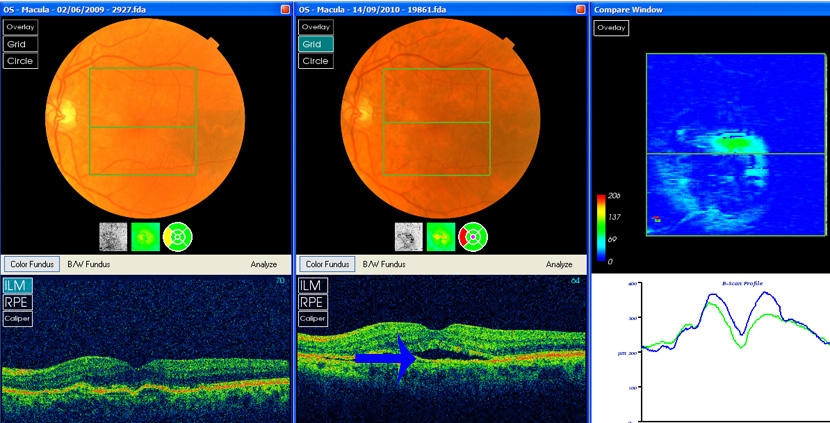

Case 19 wet armd....repeated lucentis for recurrent fluid formation

2008 Left wet age macular degeneration: distortion of vision over the previous few weeks, 6/6 right, 6/12 left. Right eye drusen only. left eye has two small lobules of retinal pigment epithelial detachment, no exudate or retinal haemorrhage, no fluorescein angiogram available

2009-10 Fluid in left eye responds to lucentis then recurs. 8 Lucentis injections in this period.

Lucentis flattened the retina ( 2009 photos on left above), green line on graph. But fluid reaccumulates needing Lucentis, as in September this year (photos right above, blue arrow/blue line on graph).